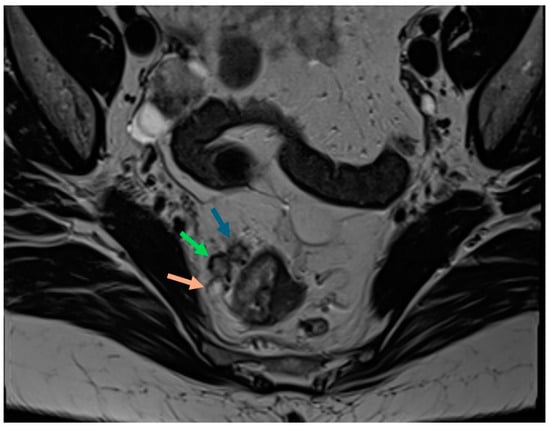

2.3. Extramural Venous Invasion (EMVI)

| EMVI | Intermediate signal within the mesorectal vessels, with a loss of normal hypointense flow void; additional features include irregular contours and increased calibre of the mesorectal vessels; should be documented both pre- and post-treatment; |